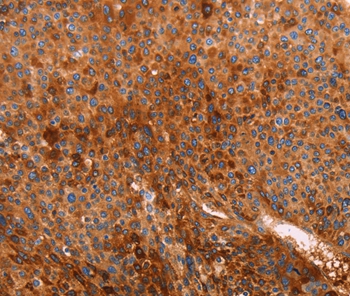

Immunohistochemical analysis of paraffin-embedded Human liver cancer tissue using #35989 at dilution 1/40.